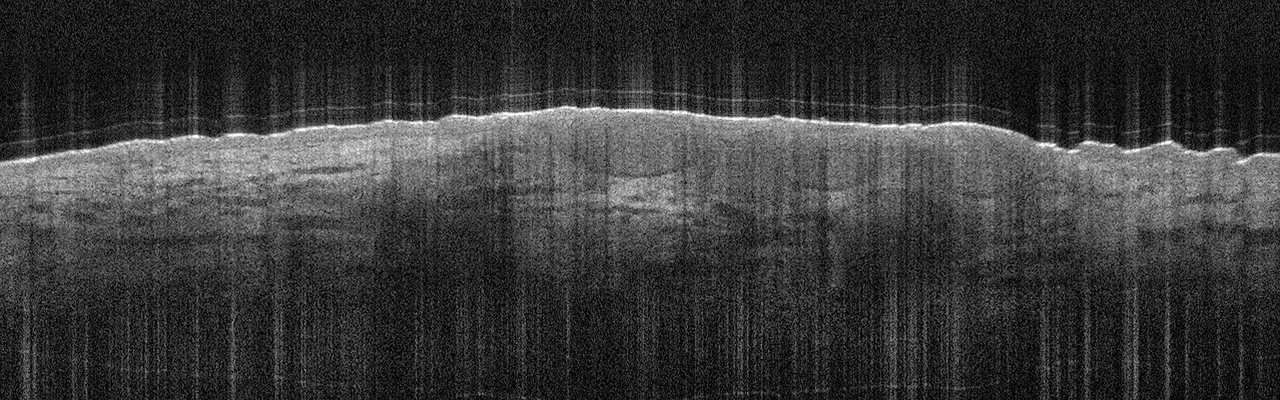

Die Tumorzellverbände des BCC erkennt man in der Aufnahme als signalarme, ovoide Nester mit dunk­lem Randsaum, die von hellem Stroma umgeben sind. Die Epidermis ist abgeflacht, Teleangiektasien kann man als kleine dunkle Löcher sehen. Eine aktinische Keratose sieht anders aus: In diesem Fall sind Hornschicht und Epidermis verdickt, oft sieht man auch weiße Streifen in der Hornschicht, so die Referentin. In Abgrenzung zum Plattenepithelkarzinom erscheint die dermoepidermale Junktion bei der aktinitischen Keratose intakt. Beim Plattenepithelkarzinom werden zudem helle Bereiche deutlich, bei denen es sich um Hornzysten handelt.

Das Einsatzgebiet muss aber nicht immer onkologisch sein. So lassen sich auch die Hornschicht- und Epidermisdicke messen sowie Porendichte, Hautrauigkeit und Hautalterungsphänomene erfassen, z.B. zur Quantifizierung von Therapieeffekten. Auch zur Kontrolle des Krankheits- bzw. Therapieverlaufs bei der Psoriasis kann das Verfahren sinnvoll sein. Para­keratosen und Neutrophilen sind in den Aufnahmen als kleine Partikel in der Hornschicht zu sehen.